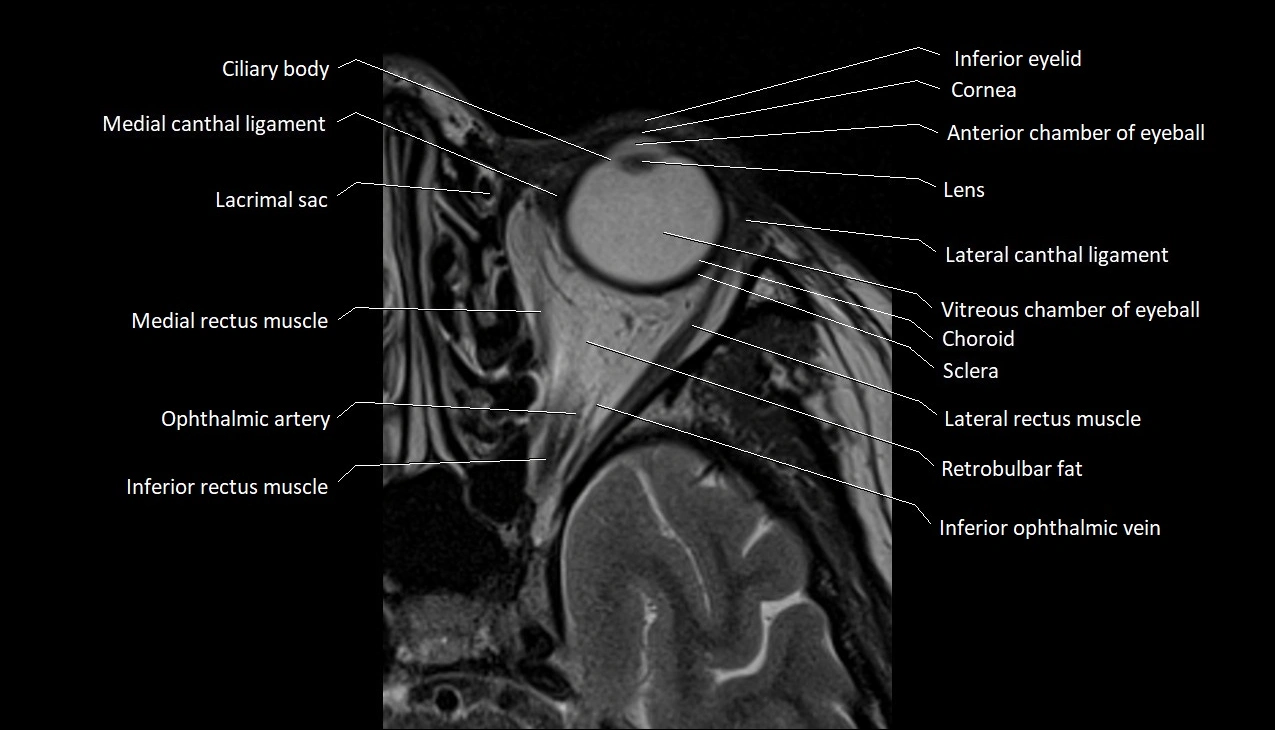

- Anterior chamber of eyeball

- Choroid

- Cornea

- Inferior eyelid

- Inferior ophthalmic vein

- Inferior rectus muscle

- Lateral canthal ligament

- Lateral rectus muscle

- Medial canthal ligament

- Medial rectus muscle

- Retrobulbar fat

- Sclera

- Vitreous chamber of eyeball

- lens of the eye